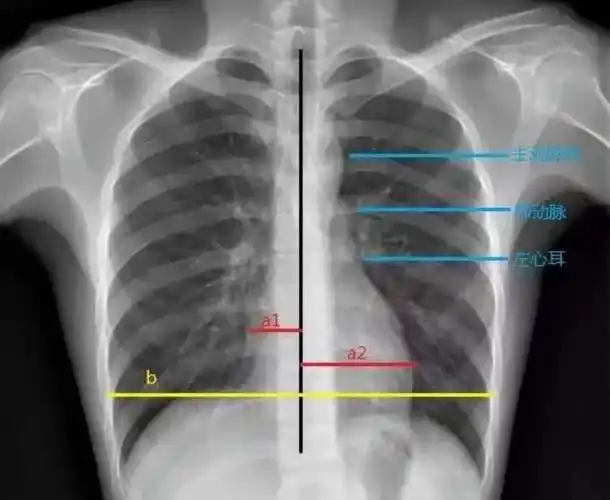

【求助】普大型心,梨形心,靴形心的片子究竟怎么看啊 - 临床执业/助理

「备考笔记」临床执业医师考试实践技能高频考点:x线平片影像诊断心脏

梨形心,靴形心,烧瓶心 :这也样看平片,想不会都难-medsci.cn

梨形心,靴形心,烧瓶心……一文教你识别

心脏增大的诊断公式和诊断方法_手机网